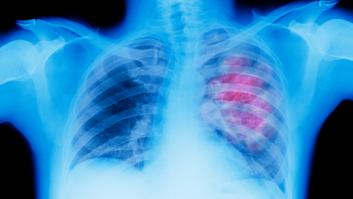

El exalcalde de Marbella, fallecido este martes, concedió junto a su mujer una entrevista en '¡De viernes!' (Telecinco) el pasado 13 de septiembre y se sinceró sobre el cáncer de pulmón que sufría.